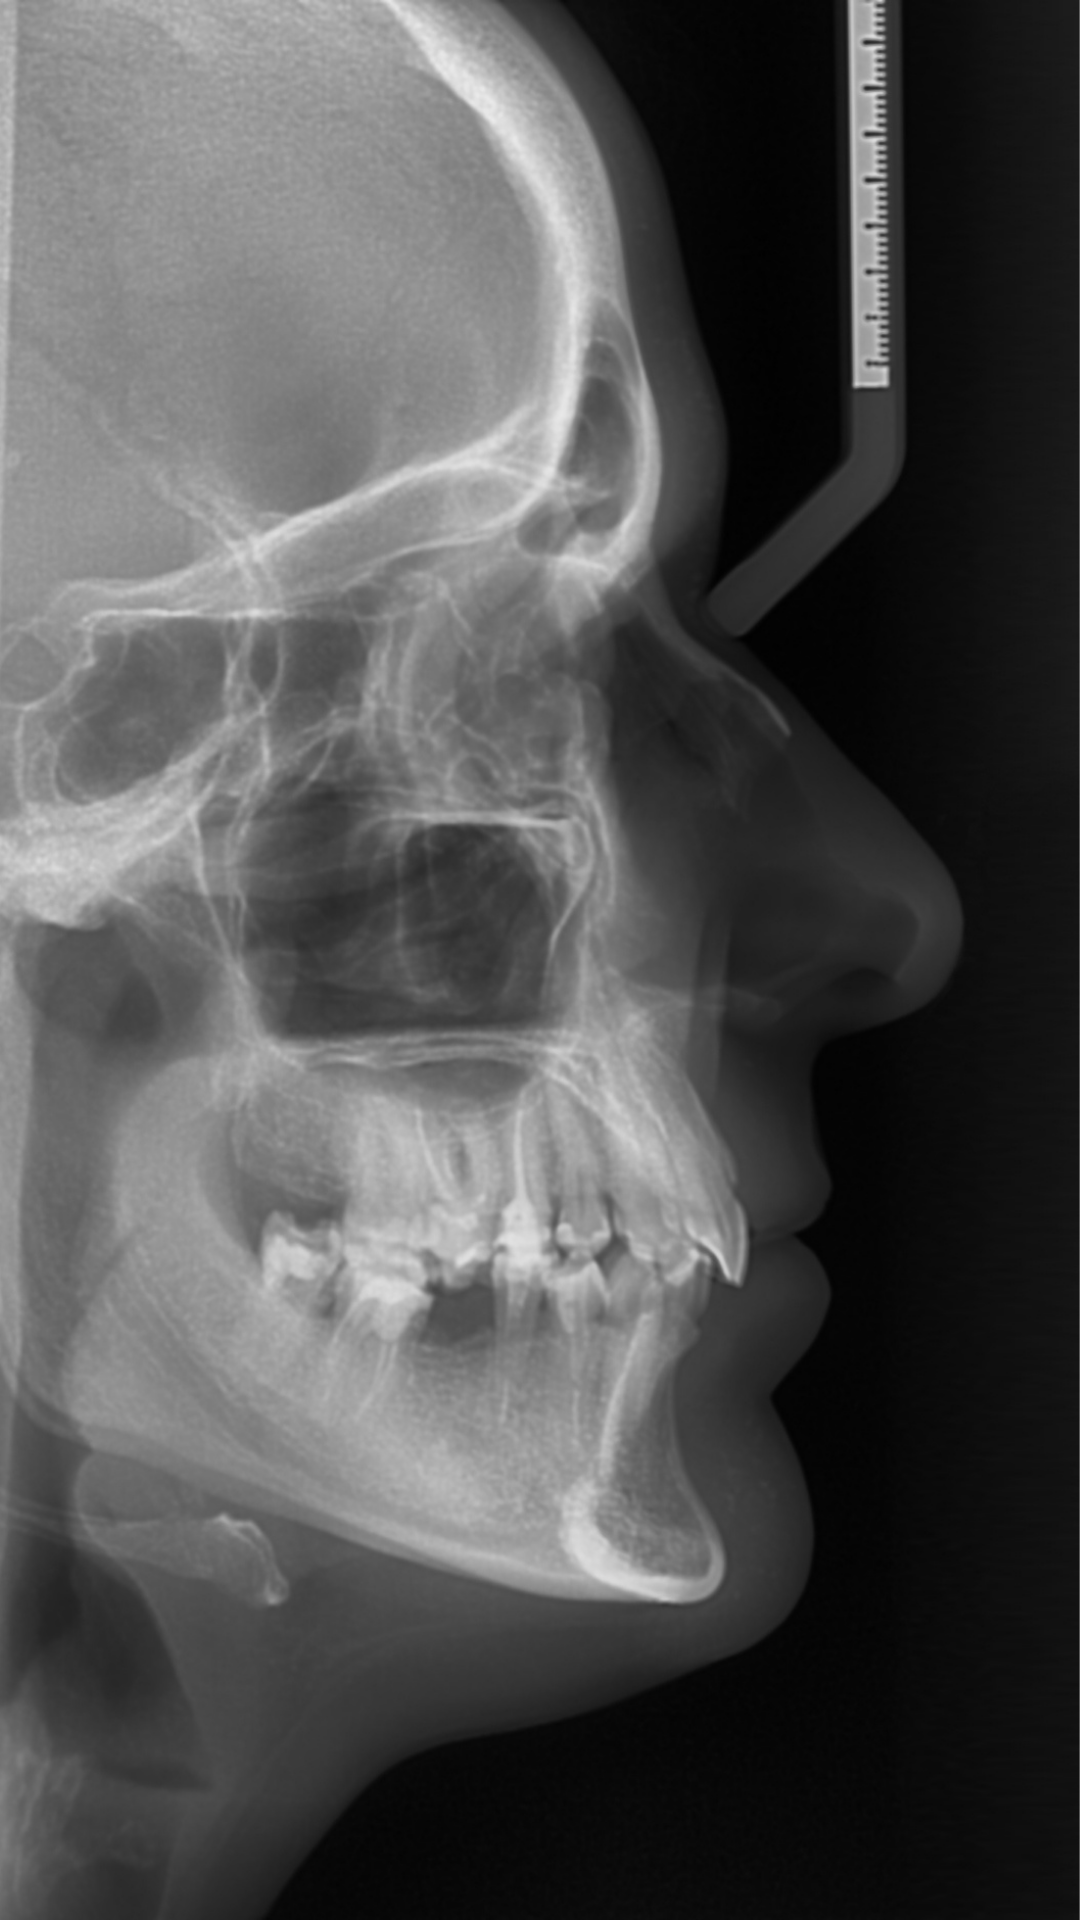

Ortodoncia, Cirugía Maxilofacial y diagnóstico integral.

Visualice ambas arcadas, senos maxilares y articulaciones en una sola toma de alta resolución.

Tomas en boca abierta y cerrada para ver el desgaste óseo sin superposiciones.

Determinación de la edad biológica (crecimiento) sin necesidad de radiografías extra de la mano.